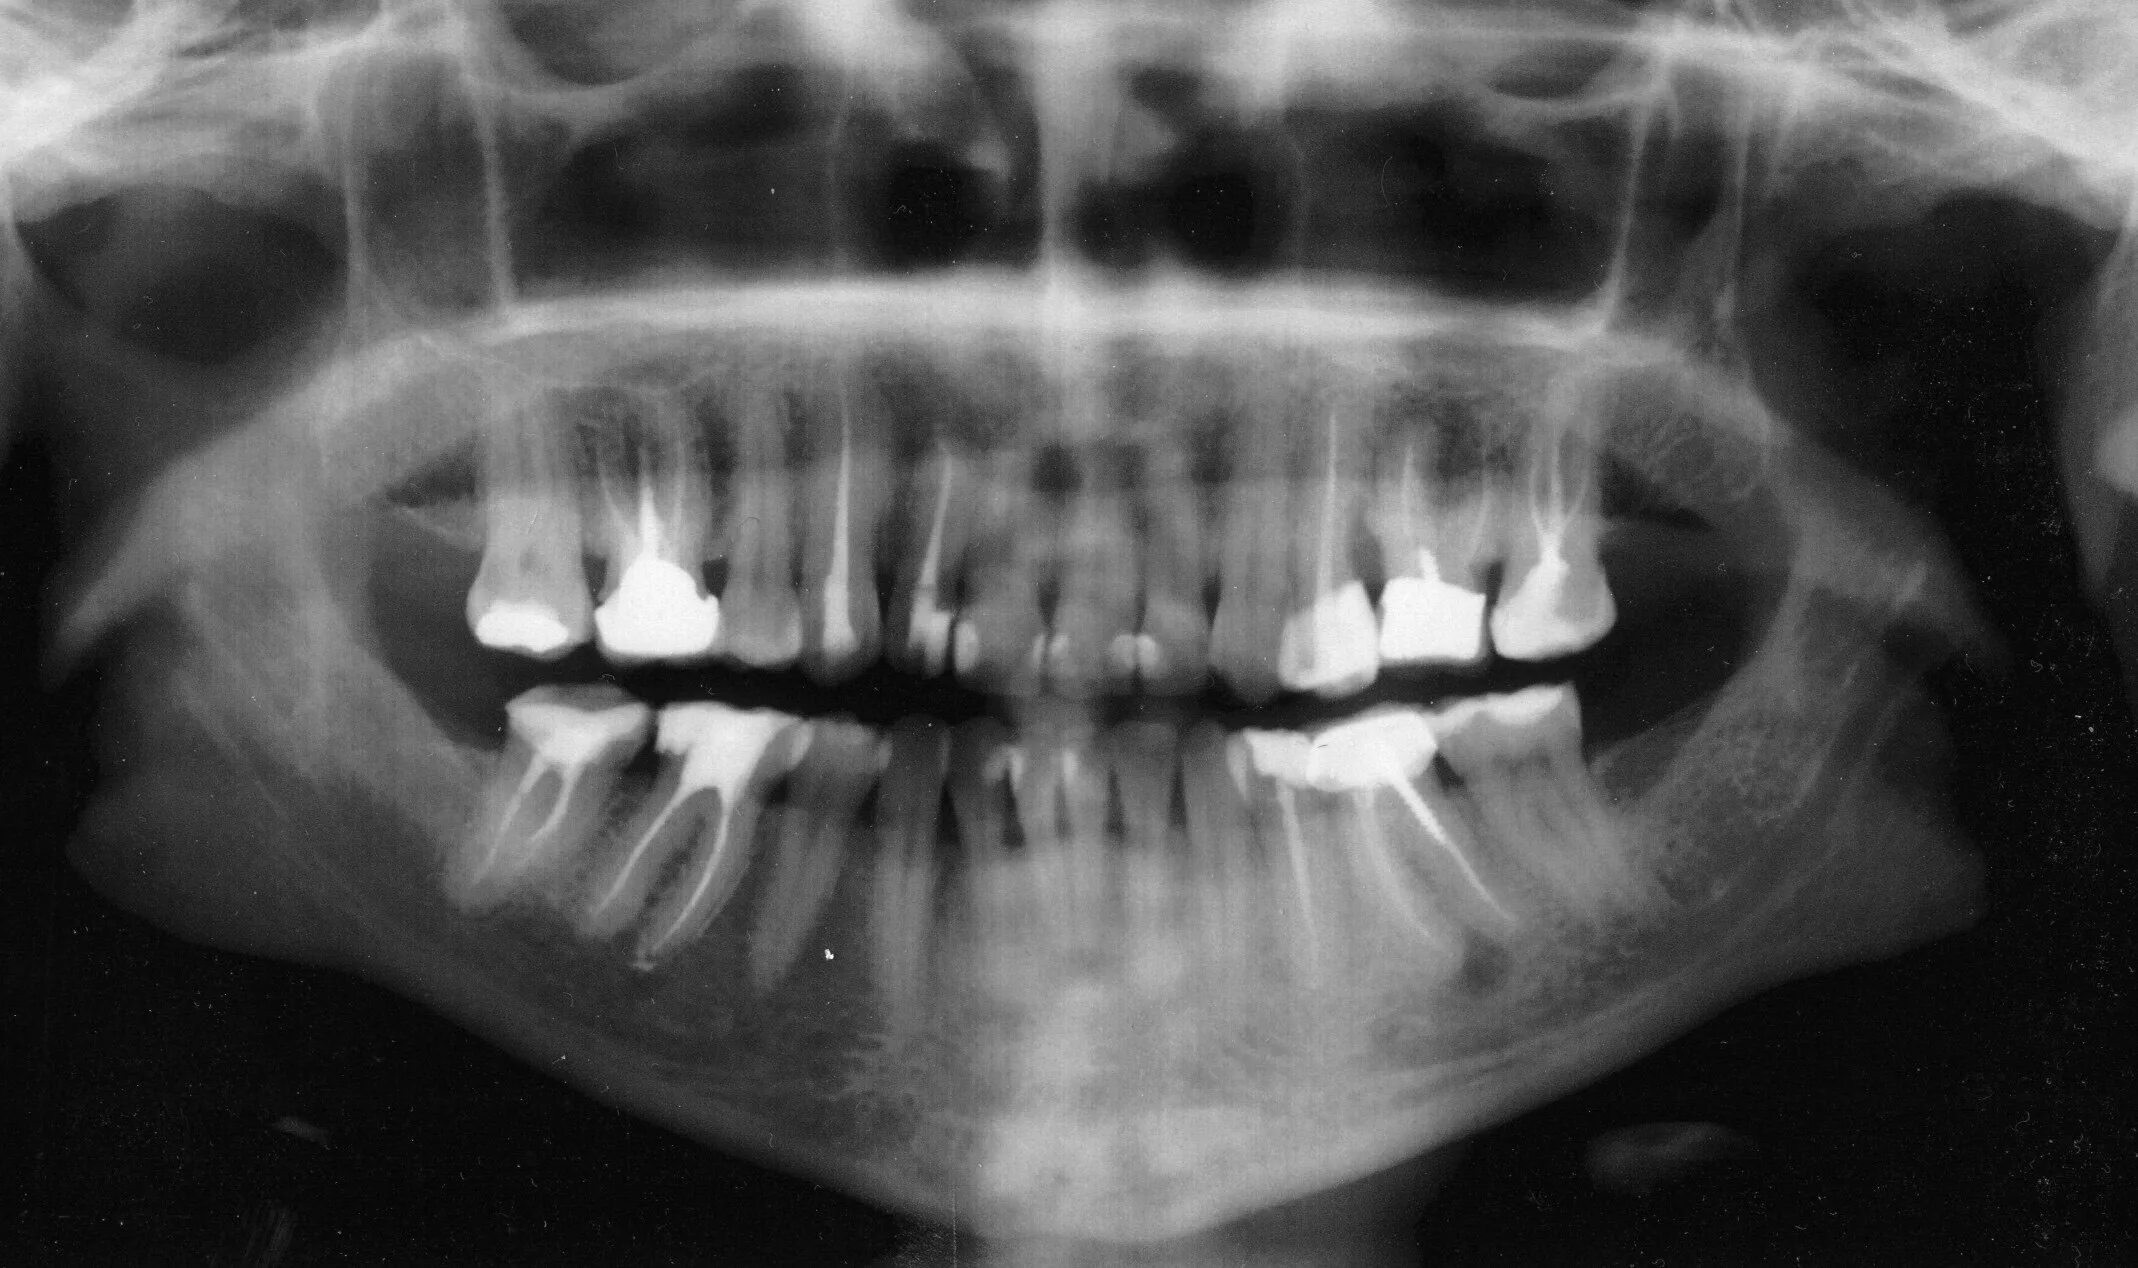

Снимок верхней и нижней челюсти